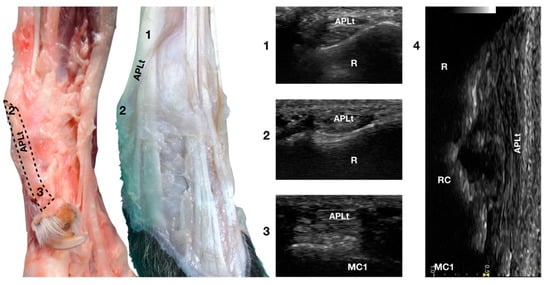

3.4.2. Abductor Pollicis Longus Tendon Ultrasonographic Anatomy (APLt)

The ulnar notch of the radius was palpated with the thumb and used to recognise the Abductor Pollicis Longus tendon (APLt) lodged inside the groove delimited by the ulnar notch. At this level, the proximal oblique portion, enclosed in the Abductor Pollicis radial groove, emerged and changed the direction of its path, becoming parallel to the medial articular surfaces of the radiocarpal, intercarpal, and carpometacarpal joints, terminating at the base of the first metacarpal bone (Figure 1a,d).

The Abductor Pollicis Longus muscle originated on the lateral surface of the radius, ulna, and interosseous membrane. Its fibres blended into a strong tendon toward the carpus, obliquely crossing the deeper ECRt and passing into the medial sulcus of the radius under the short medial collateral ligament (Figure 10).

Figure 10.

Palmaromedial and dorsal carpal faces. The oblique (1–2) and longitudinal (2–3) portions of the Abductor Pollicis Longus tendon are displayed. At the ulnar notch (2), after exiting the medial radial sulcus or the APL groove, the APLt changes inclination. Proximally, the APL follows the groove until the tenomuscular junction (1) crosses the ECRt beneath. At the ulnar notch, the oblique portion changes direction and exits the APL groove to become parallel to the medial surface of the carpus. It terminated at the base of the first metacarpal bone (MC1). On the longitudinal scan (4) obtained by aligning the probe to the medial margin of the ulnar notch, the thick APLt is seen as an undulating band rich in hyperechoic fibrillar lines. The radial (R), radiocarpal (RC), and first metacarpal (MC1) surfaces beneath are visible.

On a transverse scan, the tendon appeared as a relatively rounded, small tendon with homogeneous echogenicity and a fine fibrillar pattern at the ulnar notch of the radius. A tendon sheath surrounded this segment, creating a thin hypoechoic halo delimited by a thin hyperechoic line. The proximal oblique portion was often more difficult to visualise due to the narrow acoustic window provided by the abductor pollicis groove in which the osseous surface appeared as a U-shaped hyperechogenic line with acoustic shadow. Proximally, at the tendomuscular junction, the tendon was seen as a flat, hypoechoic structure, superficial to the ECRt. Distally, the well-defined tendon was separated from the osseous surfaces by a hypoechoic, homogeneous band corresponding to the Extensor Retinaculum. The tendon inserted medially on the proximal aspect of the first metacarpal bone with an embedded sesamoid bone, not always mineralised or present. On a longitudinal scan plane, the best starting point was the distal margin of the ulnar notch from which the tendon of the APL emerged nearly parallel to the medial surface of the carpal rows and appeared as a well-defined band with a parallel and uniformly hyperechoic fibrillar pattern. The APLt was the only one not seen to be stretched when the patient was in a standing position; a slightly wavy path was noted. At the ulnar notch, the ultrasound probe was aligned with the APL groove to follow the tendon proximally until the tendomuscular junction. The first digit was flexed and extended during the ultrasound examination to evaluate the sliding motion of the abductor pollicis longus tendon. Stressed mediolateral rotations were used to check the range of motion and adhesion or subluxation [16,17].